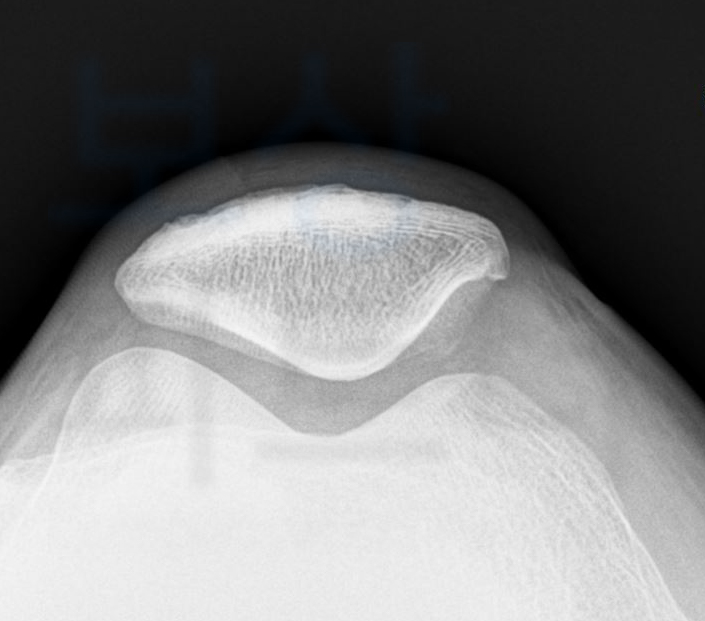

전방십자인대파열 재건술을 받은 경우 무릎관절 (슬관절)의 동요성 등으로 평가해야 합니다.

약간의 장해 기준을 함께 보시면 관절의 동요도를 평가하는 스트레스 엑스선 검사를 통해 5mm 이상의 동요관절이 확인되어야 합니다. 문제는 동요관절 측정 시 주치의마다 1mm의 차이가 발생할 수 있고 보험사에서도 내부 의료자문으로 바로 이 1mm의 차이로 장해 기준 해당 없음이나 한시장해 진단으로 지급되어야 하는 보험금의 20%만 지급되는 경우도 생깁니다.